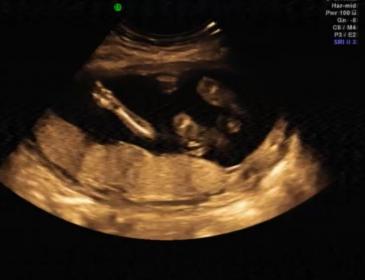

Guesses? 18 week 3D sonogram Video

I'm sooooo excited to know the gender but my husband doesn't want to find out so I'm hoping the experts here can please give me an answer :-)

p.s - if you spot any girly/boy parts please let me know what minute/sec...i'd love to see for myself too

Attachment 3296